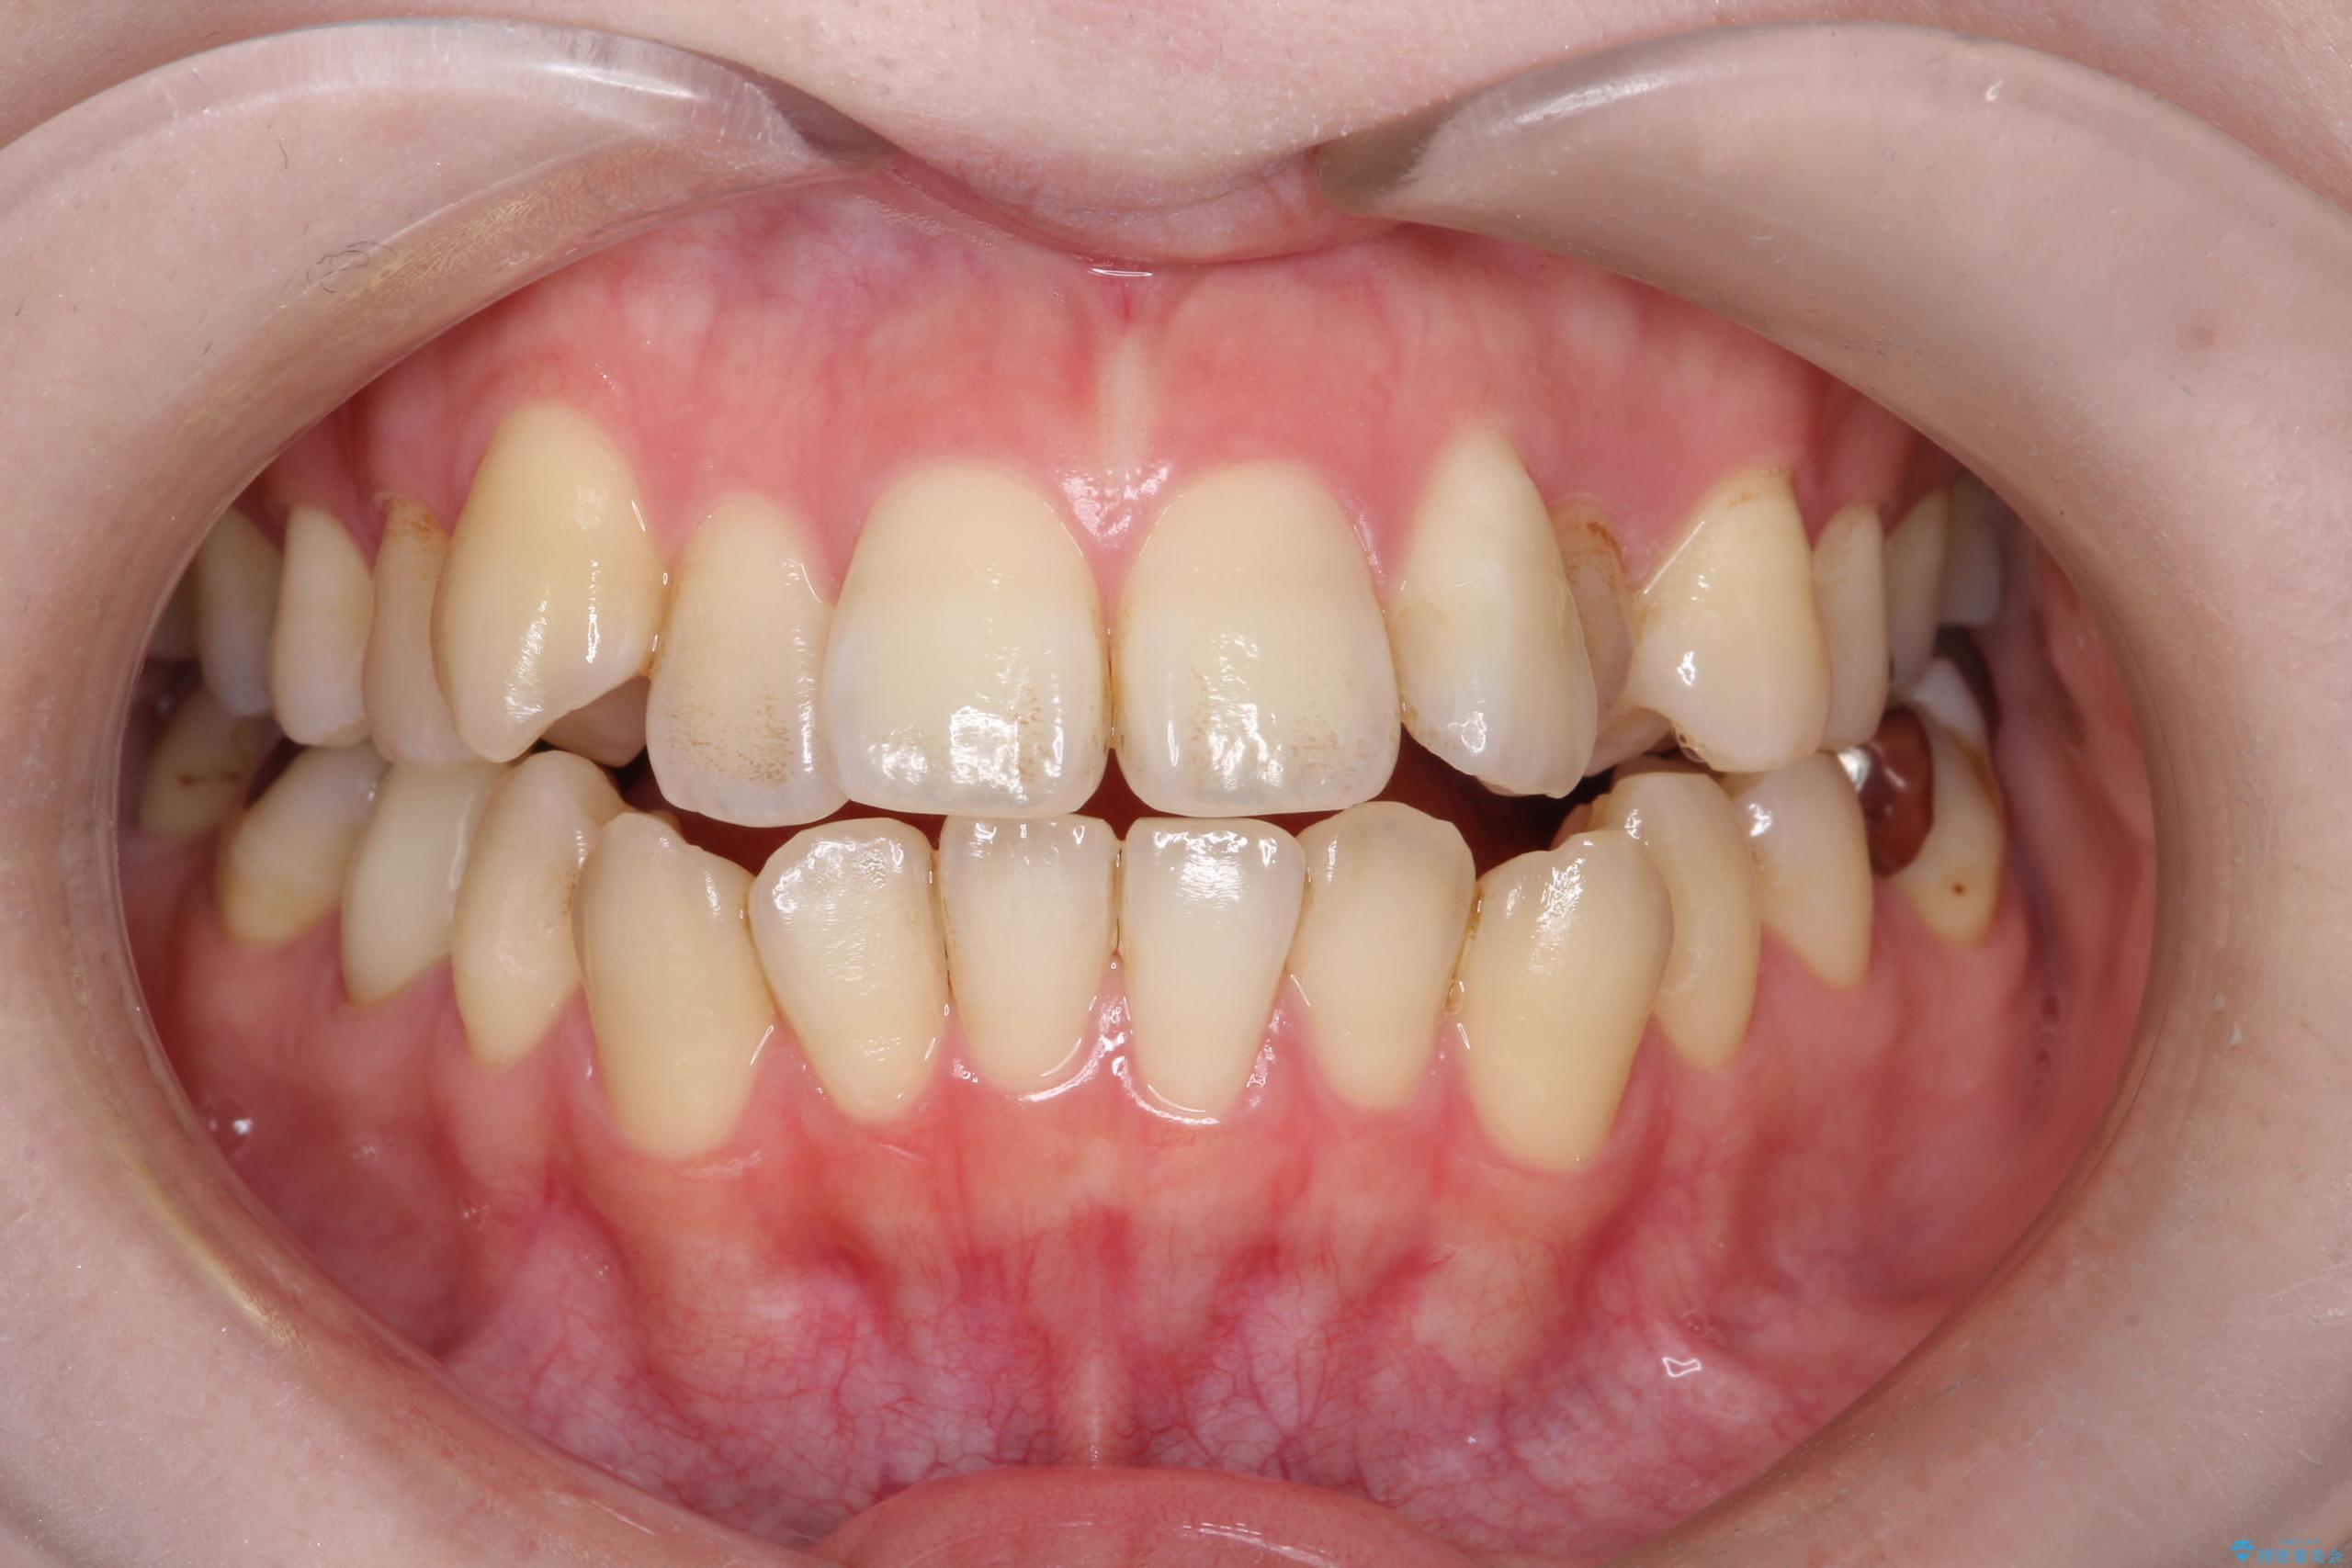

- 開咬と歯のデコボコ(叢生)、八重歯を主訴にご来院された患者様です。

開咬や歯列のデコボコが改善され、見た目だけでなく咬み合わせの機能面も大きく向上し、大変ご満足いただけました。

また、治療期間も比較的短期間で終了することができました。